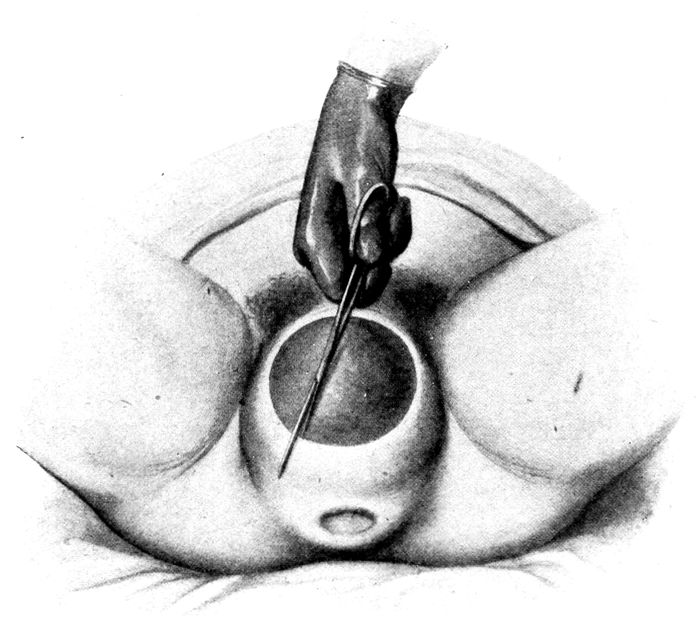

| 85. |

196 |